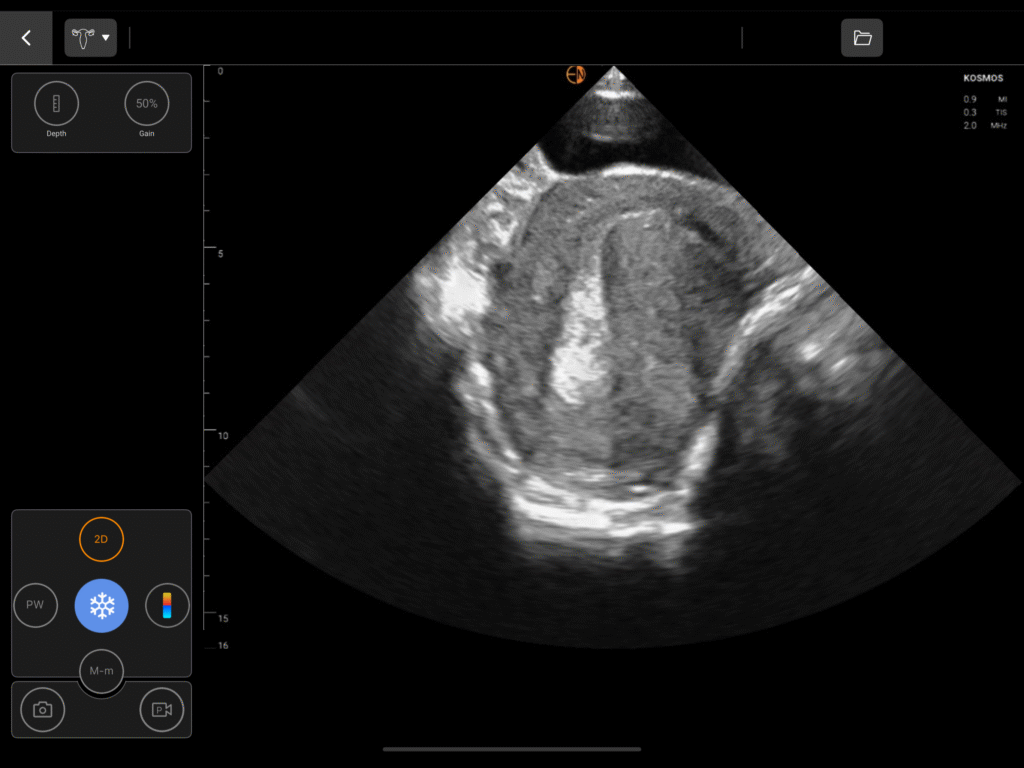

OB/GYN Image Gallery

Comprehensive OB Biometry

A complete measurement and calculation package for all three trimesters, including Gestational Sac (GS), Crown Rump Length (CRL), Biparietal Diameter (BPD), Head Circumference (HC), Abdominal Circumference (AC), and Femur Length (FL).

Dedicated measurements for the uterus, endometrium, ovaries, including volume calculations for cysts and masses, and bladder.